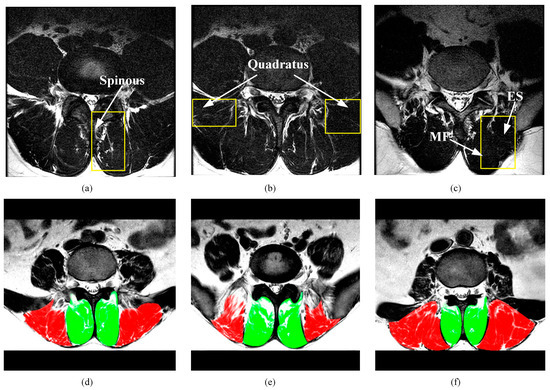

3.1. Dataset

3.4. Modules Analysis by Intra-Comparison

3.5. Comparison with other State-of-the-Art Methods

3.6. Muscle CSA Measurements